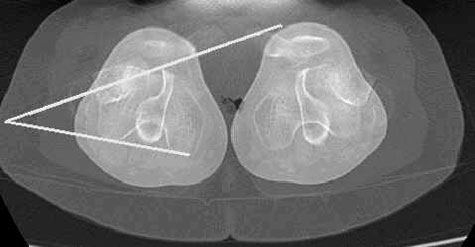

Posteriormente con esas imágenes se trazarán unos ángulos y medidas que darán el grado de torsión y rotación de fémures y tibias.

Ejemplos